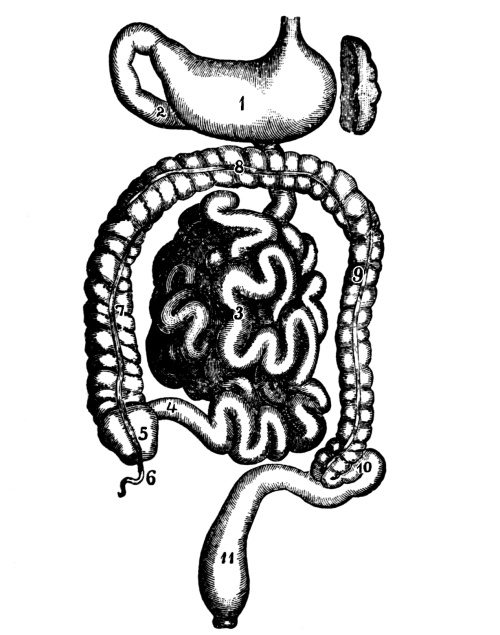

| The Abdomen and the Organs of Digestion and Excretion | 132 |

The Abdominal Cavity, 132—Muscles of the Abdomen, 132—The Peritoneum, 134—Abdominal Regions, 134—Salivary Digestion, 136—The Pharynx, 139—The Esophagus, 138—The Stomach, 138—Gastric Digestion, 139—Vomiting, 140—Intestinal Canal, 141—The Small Intestine, 142—Intestinal Digestion, 143—Absorption in Intestine, 144—The Large Intestine, 145—Food and Metabolism, 147—The Liver, 149—The Gall-bladder, 152—The Pancreas, 153—The Spleen, 153—The Suprarenal Capsules, 154—The Kidneys, 155—The Urine, 156—The Ureters, 159—The Bladder and Urethra, 159. |